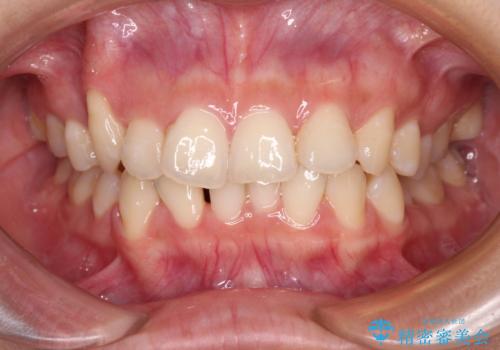

- 八重歯と上顎正中のズレを気にして来院された患者様です。

インビザラインによる矯正治療を希望されたため、八重歯改善のための抜歯矯正部分や上顎正中の大幅に位置移動は、補助装置やワイヤー矯正を併用し、その後はインビザラインにて行うこととしました。

骨格的に下顎が左側に変位していたため、上下正中を合わせることは困難であることは分かっていましたが、可能な限り合わせることができました。